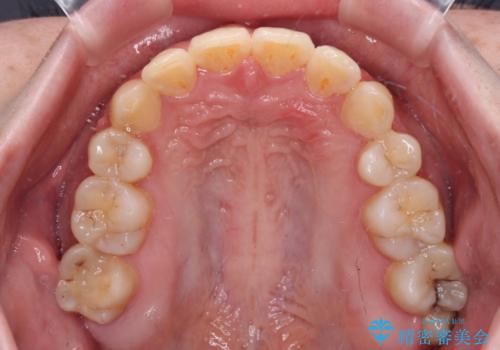

インビザラインが続けられない ワイヤー矯正での抜歯矯正 その1

- 八重歯やデコボコをインビザラインで治療したいとのことで来院された患者様です。

インビザライン単体で治療を行うには叢生が強いと判断されたため、事前にワイヤー装置で抜歯矯正を行い、ある程度改善してからインビザラインにて仕上げていくこととしました。